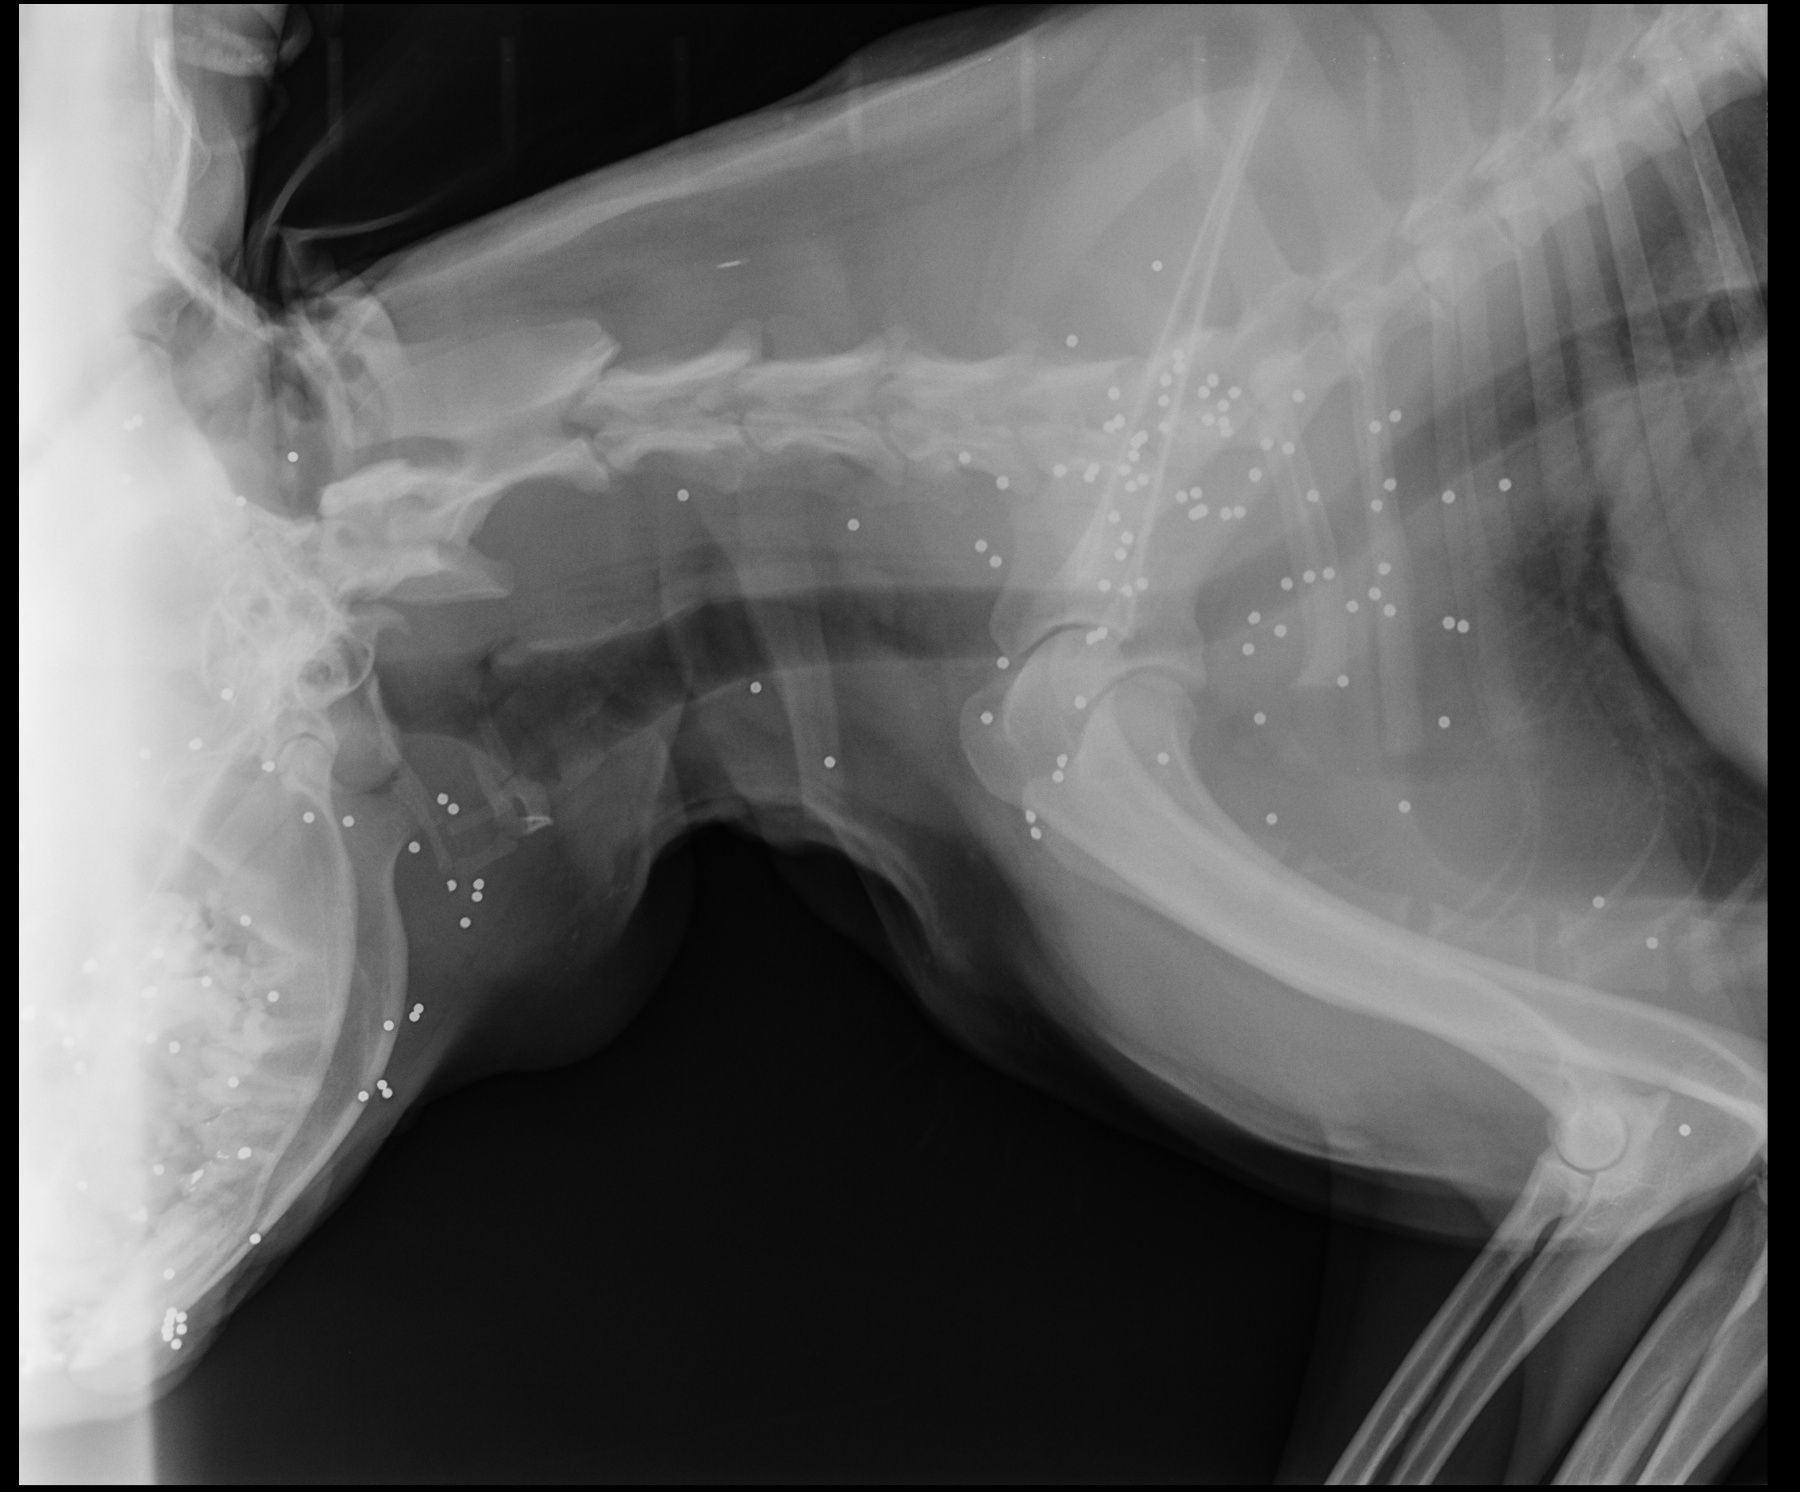

O τραυματισμένος σκύλος που μεταφέρθηκε για νοσηλεία στο κτηνιατρείο του Στάθη Πιτταρά έχει στο κεφάλι, στον τράχηλο και στο αριστερό του πόδι περισσότερα από 160 σκάγια.